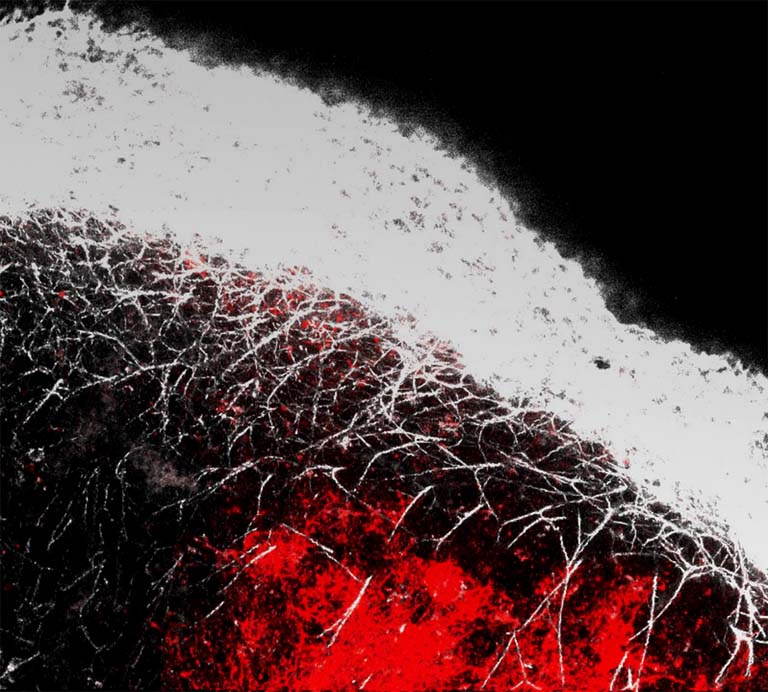

Vaccine targeting to the lymph node, an immune cell rich organ, is critical for vaccine efficacy. The images was taken 7 days after a preventive HIV vaccine was administered to mice through a dermal nanoparticle delivery device and shows vaccine accumulation in the lymph node. The vaccine that has reached the lymph node would interact with (teach) the immune cells to produce strong vaccine specific immune responses necessary to prevent a future infection taking us one step closer to a world without HIV.